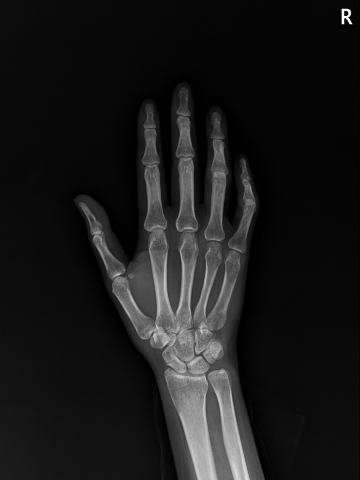

수술후

2023.01.04

수술전

2022.04.29

ㆍ환자 동의를 받은 자료이며, 이미지 사진은 실물과 다를 수 있습니다.